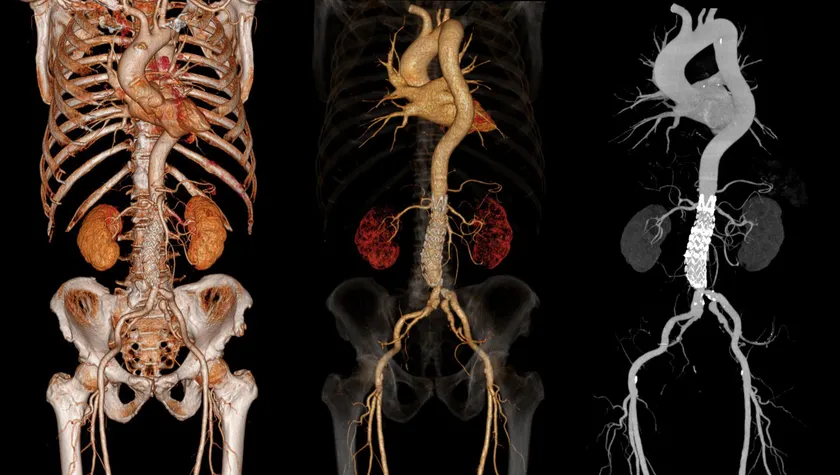

3Dimage

(3)画像だけでなく、動画での提供もできること

他社の遠隔画像システムの場合、診断結果はレポート(文字情報)とキー画像(送信画像のjpgなど)での提供と、せいぜい直交MPRが作成されるのみでした。「画像診断ラウンジ」はraw dataのまま送信可能で、キー画像も送信された画像だけでなく、動画(mp4など)、三次元画像(VR,MIPなど)、再構成画像(直交およびcurved MPR)などの提供もできるため、診断により役立てることができます。DICOM viewerはOsiriXMD(Macのみ)を使用しており、多くのポストプロセス画像をキー画像として提供可能となっています。